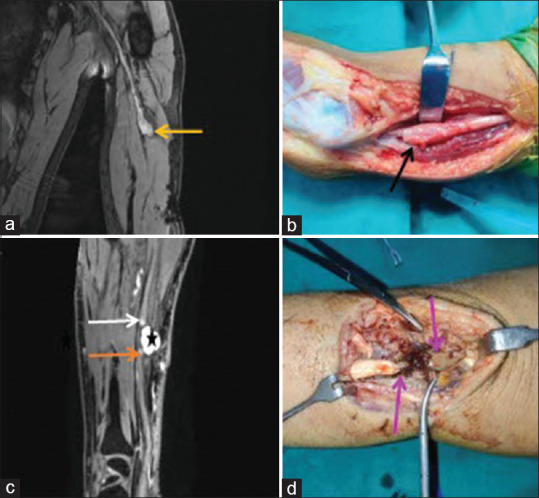

背景和目的:磁共振神经成像(MRN)允许神经的直接可视化,这可以有助于周围神经疾病的诊断、表征和定位。我们计划对转介行核磁共振的周围神经损伤患者进行研究,并将核磁共振结果与神经传导研究(NCS)对各种局灶性神经疾病的结果进行比较。方法:这项前瞻性研究进行了超过1年半,涉及58名临床诊断为局灶性周围神经病变的受试者,他们被转介到放射诊断和影像学部门进行MRN检查。MRN检测到的局灶性周围神经病变范围与NCS和/或肌电图结果以及手术和/或组织病理学结果相关并进行比较。采用χ 2检验和Fisher精确检验评价MRN与NCS结局的相关性。结果:该研究确定了广泛的周围神经病变。在58例受试者中,52例(89.6%)发现异常,而6例(10.3%)患者未显示任何明显异常。50例(86.3%)患者在MRN和NCS上均表现异常,5例(8.6%)患者在MRN和NCS上均未表现异常。2例(3.4%)MRN异常但NCS结果正常,1例(1.7%)MRN正常但NCS结果异常。在58例mri检查中,25例发现臂丛受累。结论:核磁共振成像是评价周围神经病变的一种高度敏感的工具。其与NCS和术中发现的相关性进一步支持了其临床应用。在周围神经病变的诊断过程中,3t核磁共振成像应被视为一种关键的成像方式。此外,它还可以作为规划治疗干预措施和评估各种患者亚群预后的有价值的指南。

Results: The study identified a broad spectrum of peripheral nerve pathologies. Out of 58 subjects, abnormalities were found in 52 (89.6%) subjects, whereas six patients (10.3%) did not show any significant abnormalities. Fifty patients (86.3%) showed abnormalities on both MRN and NCS, while five patients (8.6%) did not show any abnormalities on either MRN or NCS. Two patients (3.4%) showed abnormalities on MRN but had normal NCS results, and in one case (1.7%), MRN was normal but NCS showed an abnormality. Out of the 58 MRN examinations, 25 were found to have brachial plexus involvement.